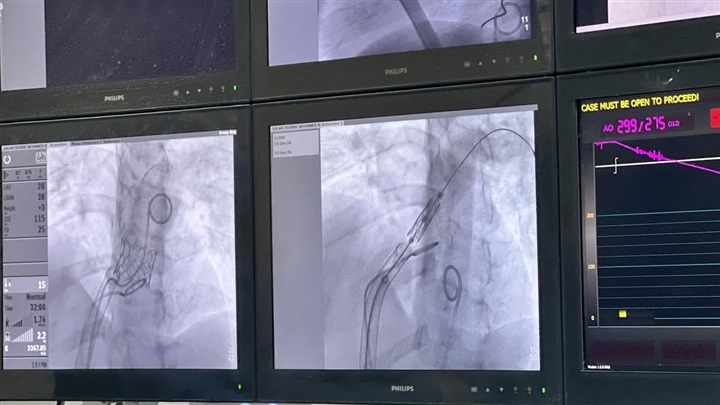

أعلنت الهيئة العامة للرعاية الصحية عن نجاح إجراء أول عمليتين لزرع الصمام الرئوي عن طريق القسطرة القلبية التداخلية، وذلك لأول مرة ضمن منظومة التأمين الصحي الشامل، داخل مستشفى النصر التخصصي التابع للهيئة بمحافظة بورسعيد.

وأشار بيان الهيئة أن هذه التقنية من أدق وأحدث التدخلات الطبية عالميًا، حيث تمثل بديلًا آمنًا وفعالًا لجراحات القلب المفتوح المتكررة، خاصة في حالات العيوب الخلقية المركبة بالقلب.

وفيما يتعلق بالحالات الطبية، فقد خضعت الحالة الأولى، (18 عامًا)، لزرع الصمام الرئوي بنجاح بعد تاريخ مرضي تضمن 7 تدخلات سابقة منذ الولادة، وغادرت المستشفى بعد 24 ساعة فقط في حالة مستقرة.

أما الحالة الثانية (16 عامًا)، فكانت تعاني من عيوب خلقية مركبة بالقلب، وخضعت سابقًا إلى 4 جراحات قلب مفتوح ومرتين قسطرة قلبية، وتم تركيب الصمام الرئوي بنجاح، لتغادر المستشفى بعد 72 ساعة في حالة صحية مستقرة تمامًا.

وقد أُجريت العمليتان بنجاح على يد الفريق الطبي الوحيد المعتمد في افريقيا في اجراء زراعة الصمام الرئوي عن طريق القسطرة، بقيادة الدكتور عبد الرحمن العفيفي، الخبير الأول في مصر في زراعة الصمامات الرئوية المختلفة ورئيس قسم قلب الأطفال والقسطرة التداخلية للعيوب الخلقية للأطفال والكبار بمستشفى النصر التخصصي ومستشفيات مجدى يعقوب، وبمشاركة الاستشاريين الدكتور شريف سليمان والدكتور محمد توفيق، إلى جانب فريق من اخصائيي قلب الأطفال ضم الدكتورة وفاء أبو الخير، والدكتورة إلهام ربيع، الدكتورة هايدي حسن، الدكتور إيفان عماد، الدكتورة أسماء الباز، واستشاري التخدير الدكتور أحمد سمير، وبمعاونة فريق رفيع المستوى من التمريض والفنيين ضم الأستاذة آية إبراهيم الغريب مسؤول عمليات القسطرة، الأستاذة راضية علي اخصائي تمريض، وفنيي التمريض سمر أحمد إبراهيم، زينب حامد محمد، شيماء محمد عطا، وفني الأشعة أ. محمود المغربي.